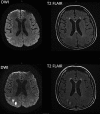

Posterior reversible encephalopathy syndrome (PRES) is a neurological syndrome characterized by an altered level of consciousness, headaches, seizure, and visual changes. PRES has several different etiologies, including malignant hypertension, eclampsia, and certain medications. Here, we describe a 41-year-old woman who presented with altered mental status. She had a preliminary diagnosis of serotonin syndrome as she was on many different serotonin-sparing agents, but her imaging findings were consistent with PRES. After her medications were reviewed and the causative agent was removed, the patient's neurological exam and imaging findings improved, and she returned to her baseline. To our knowledge, this is a unique case of PRES caused by serotonin syndrome secondary to venlafaxine usage.